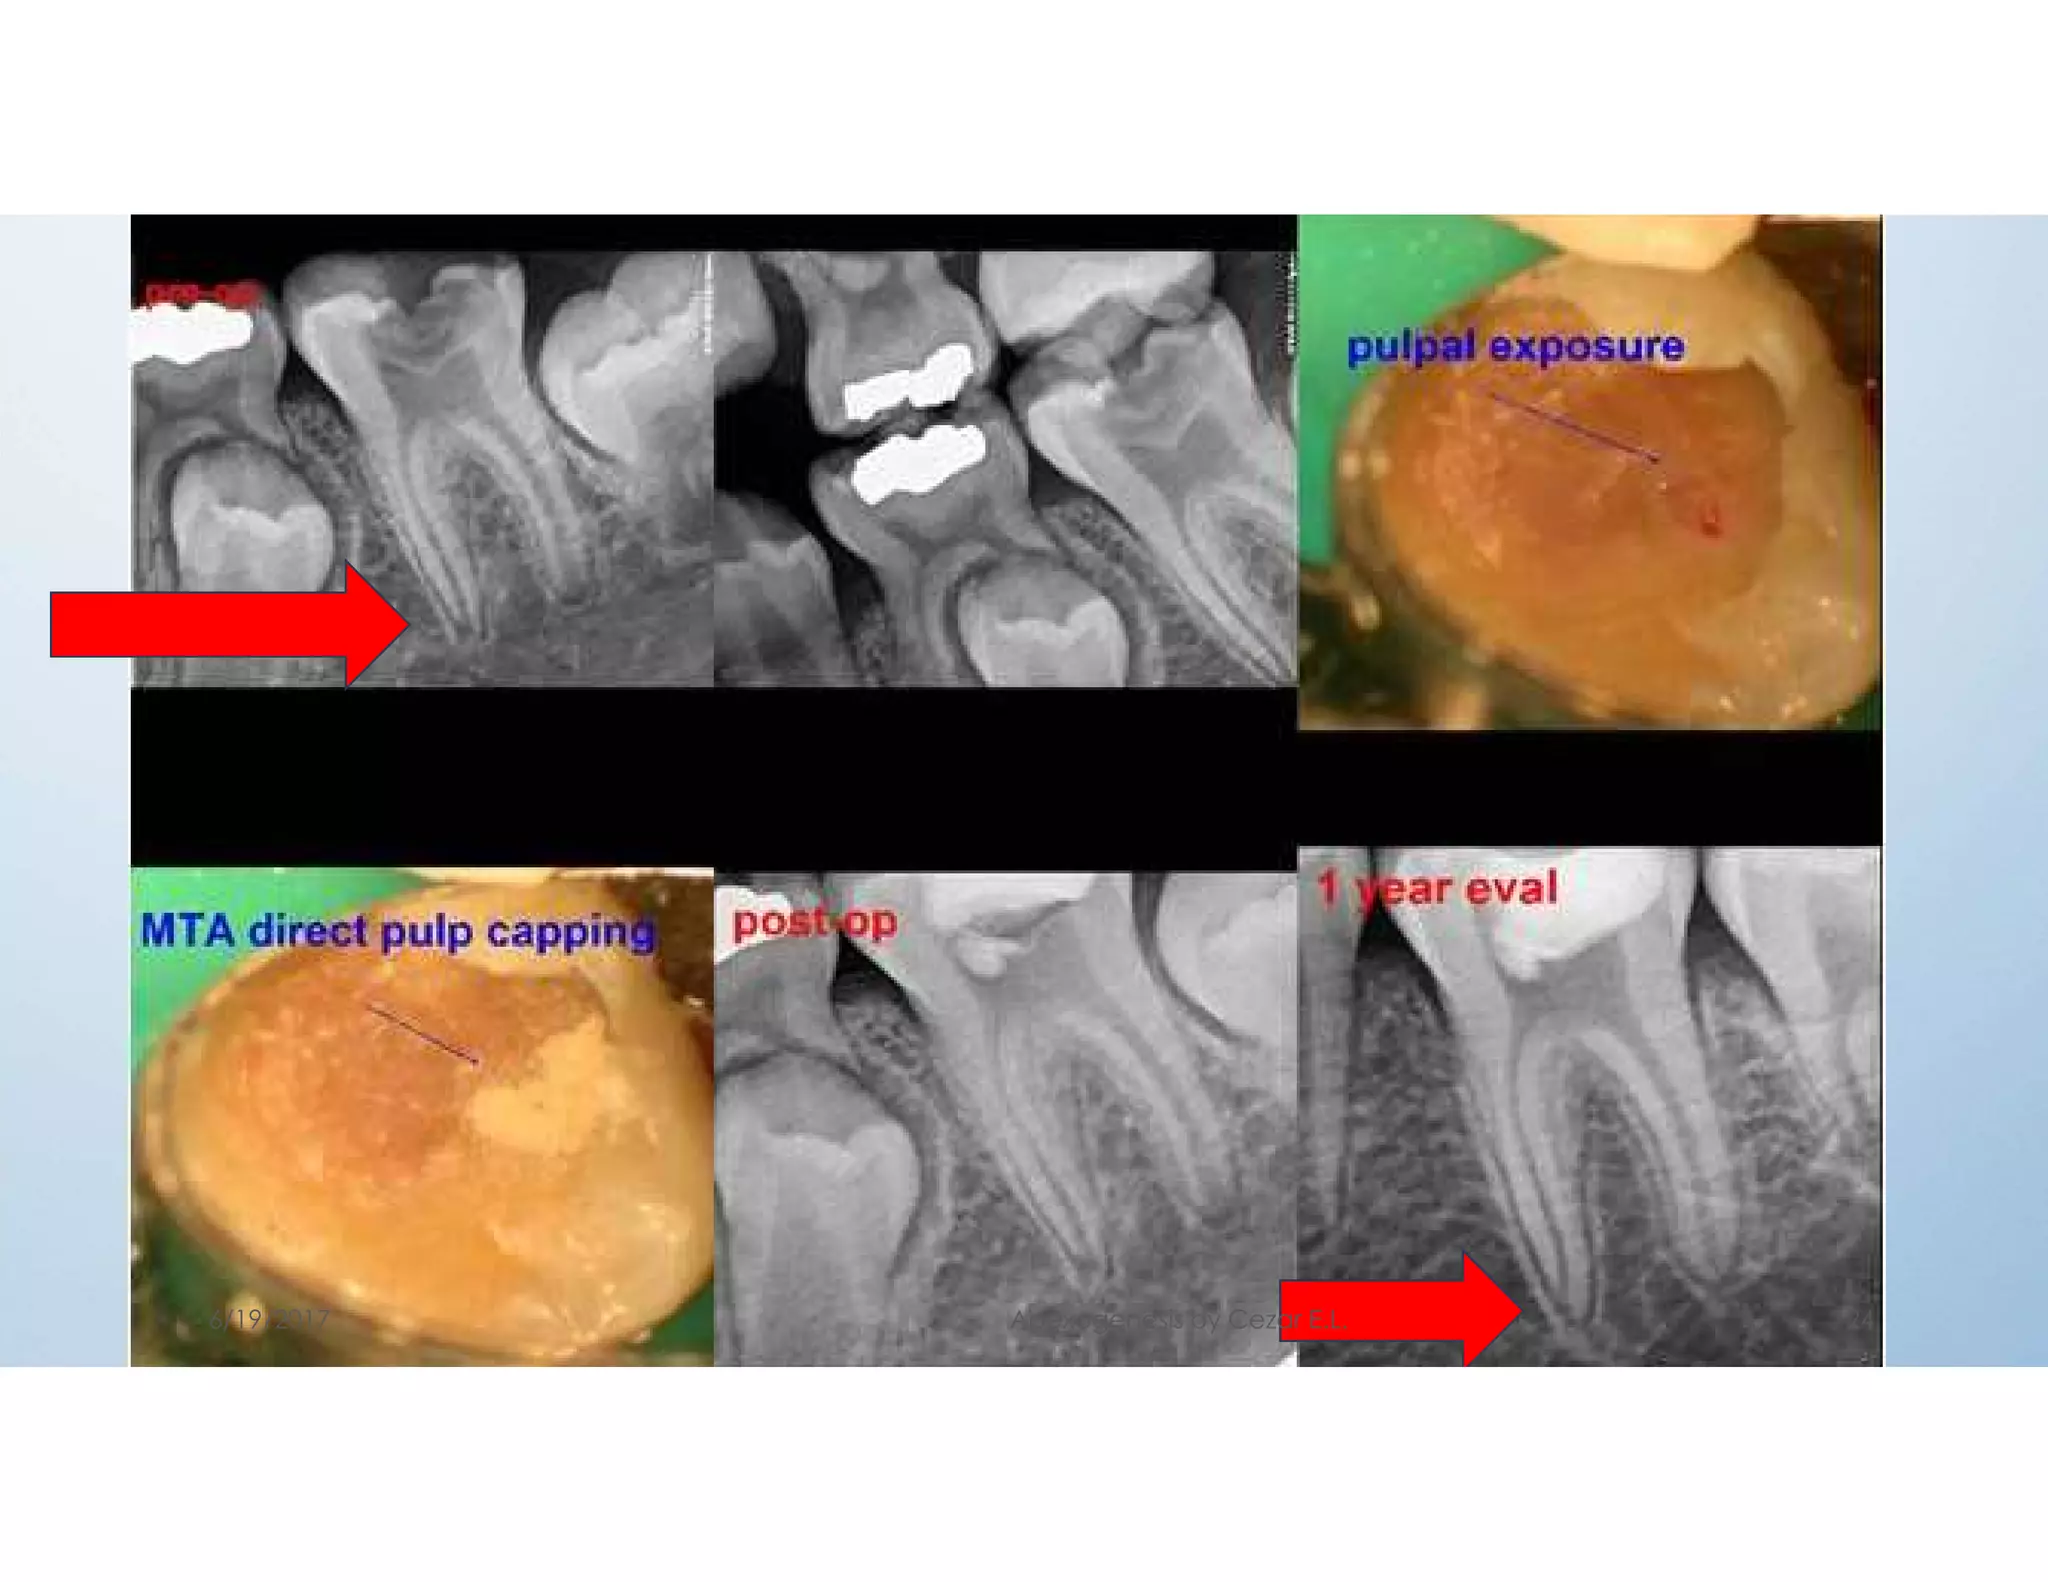

Defined as a procedure in which the exposed vital pulp is

covered with a protective dressing or base placed directly

over the site of exposure in an attempt to preserve the pulp

vitality.

OBJECTIVES: a) preservation of vitality of the radicular pulp.

b) relief of pain in patients with acute pulpagia.

c) ensuring the continuity of normal apexogenesis

in immature permanent teeth.

2- Direct pulp capping

INDICATIONS:

a) asymptomatic conditions.

b) small exposure less than 0.5mm in diameter

c)haemorrhage from the exposure site is easily controlled.

d) the exposure occurred is clean

CONTRAINDICATION:

Large carious exposure ,irreversible pulpitis, necrotic pulp